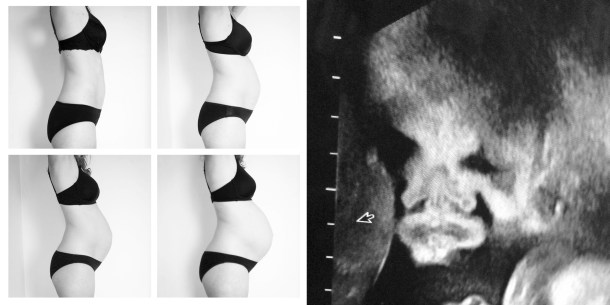

> Echo … echo! Bij de gynaecoloog binnenwippen voor een echo blijft speciaal. Je valt er Alice in Wonderland-gewijs in een andere wereld via je navelgat – een die je anders nooit te zien krijgt. Plots onthult een scherm jouw kindje, wit op zwart. Je hele buik kleurt er warm van, ondanks de koude geltopping erbovenop. Toch borrelen er ook vragen vanbinnen, zoals “Heeft hij wel een neus? Want we zien alleen een zwart gat.” en “Gaat hij echt lijken op die 3D-foto – nooo?! Precies een gesmolten wassen beeld uit Madame Tussauds.” Maar hoe hij er ook uitkomt of uitziet, voor ons is hij nu al perfect!

> Geen gemiste kans. “Had ik maar meer foto’s van mijn bolle buik”, puffen moeders vaak achteraf. Dus ik vat de drachtige koe bij de horens en vraag The Talented Mr. Ydiers – mijn neef slash fotograaf – om wat foto’s te nemen. Buiten. In het bos. In de mist. In de vrieskou. Aaw, mijn vingers en neus kraken er bijna af! Deze sessie kan alvast tellen als les in pijn verbijten. Maar het resultaat bevalt gelukkig! Nu alleen nog puffen voor het échte werk. Het wordt spannender en spannender … ook rond mijn meegroeiende moederpoep.